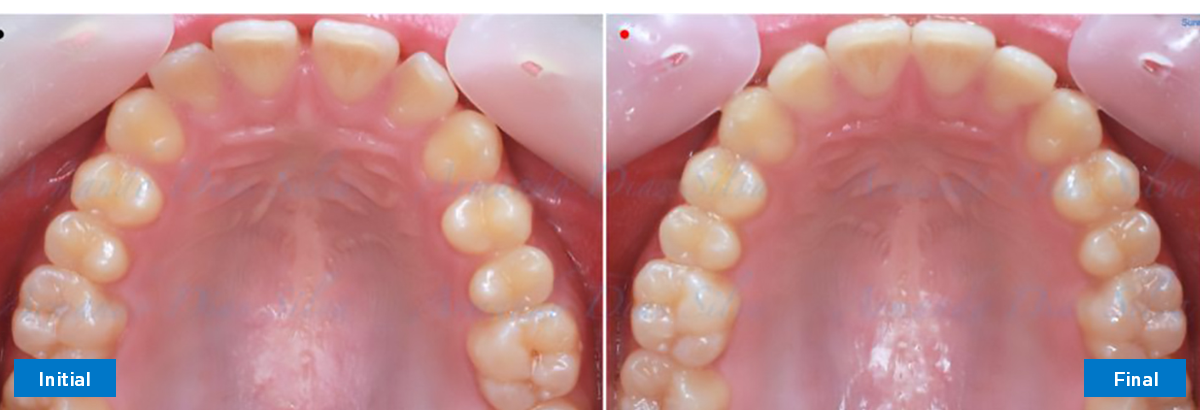

• Espaciamiento leve de las arcadas superior e inferior (deficiencia transversal de 3,45 mm)

• Deficiencia transversal maxilar leve (3,45 mm)

• Alinear y nivelar sin extracciones

• Desrotar y distalizar los molares superiores

• Retruir los incisivos superiores

Se logran todos los objetivos principales:

• Molares de clase I logrados con distalización y sin elásticos

• Sin expansión maxilar, respetando la envoltura periodontal